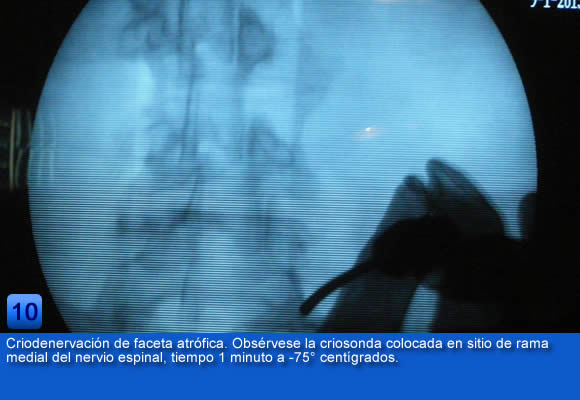

Estas medidas suponen un alivio satisfactorio para un gran número de pacientes, pero cuando no se obtiene un gran alivio del dolor a corto plazo, se puede optar por un tratamiento más selectivo como es la criodenervación percutánea facetaría lumbar, que permite un alivio mas duradero para que los pacientes puedan reanudar sus actividades cotidianas.

Como tratamiento sintomático es temporal y debe de ir acompañado de una reducación paralela de la espada. Pero una buena selección de los pacientes y una correcta indicación, considerando que la mayoría de las veces se aplica a pacientes con dolor lumbar crónico en el que suelen existir diversas implicaciones, obtienen resultados duraderos en el tiempo ayudando a disminuir el impactó sobre la actividad cotidiana de los pacientes con dolor lumbar crónico y el numero de pacientes que se han de someter a cirugía abierta espinal.